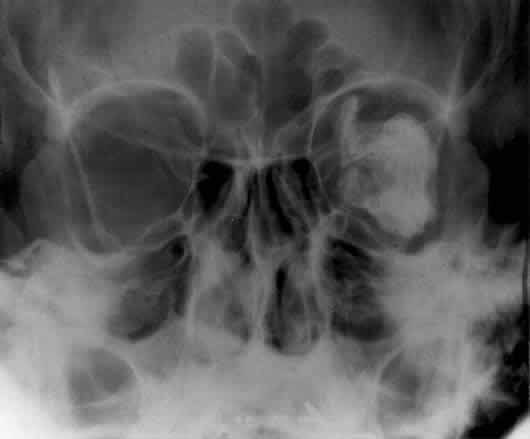

The posterior segment of the lateral wall courses posterior medially and can be seen in anterior projections such as the Caldwell view. This view allows direct visualization of the greater sphenoid wing contribution to the lateral wall. Bone density changes in the greater wing of the sphenoid, such as from a meningioma, can be detected. Fractures of the lateral orbital wall can occur from blunt trauma to the malar prominence. The zygomatic complex fracture (tripod) results from separation of the zygomatic-frontal, zygomatic-temporal, and the zygomatic-maxillary sutures. These fractures are associated with an inferior displacement of the malar prominence and a rounded lateral canthus (Figs. 8 and 9).

Fig. 8. A zygomatic complex fracture (tripod) after blunt trauma to the right cheek. Note the right zygoma is inferiorly displaced. (a, zygomatic-frontal suture separation; b, orbital rim disruption; c, opacification of maxillary sinus)

Fig. 9. Bilateral zygomatic complex and LeFort II fracture after reduction using fixation plates. Caldwell projection shows good alignment of orbital margin and zygomatic bones.